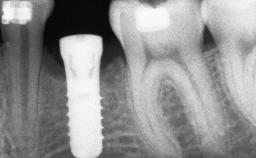

# of Implants 8

Bone Augmentation Horizontal|Sinus Floor Elevation|Staged|Vertical

Augmentation Materials Autogenous chips|Autogenous block(s)

Bone Volume Deficient vertically or deficient vertically AND horizontally